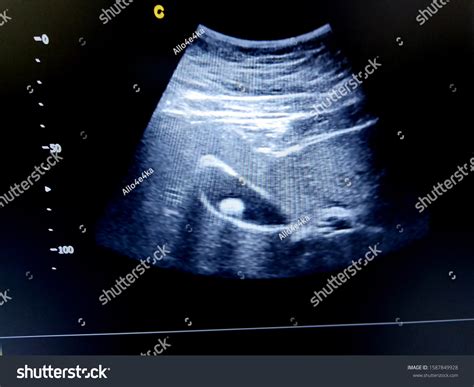

The primary advantage of using an ultrasound for gallbladder problems is its unmatched ability to identify gallstones. Because gallstones are often calcified or dense, they reflect sound waves differently than the surrounding fluid-filled gallbladder, making them clearly visible on the monitor. Furthermore, ultrasound is highly efficient at detecting signs of inflammation, such as a thickened gallbladder wall or the presence of fluid around the organ, which are indicators of cholecystitis.

Cholelithiasis (Gallstones) Highly reflective (echogenic) spots within the gallbladder, usually with a characteristic "acoustic shadow" behind them.

Cholecystitis (Inflammation) Thickened gallbladder walls, fluid accumulation around the gallbladder, or a positive "sonographic Murphy’s sign" (tenderness when the probe is pressed).